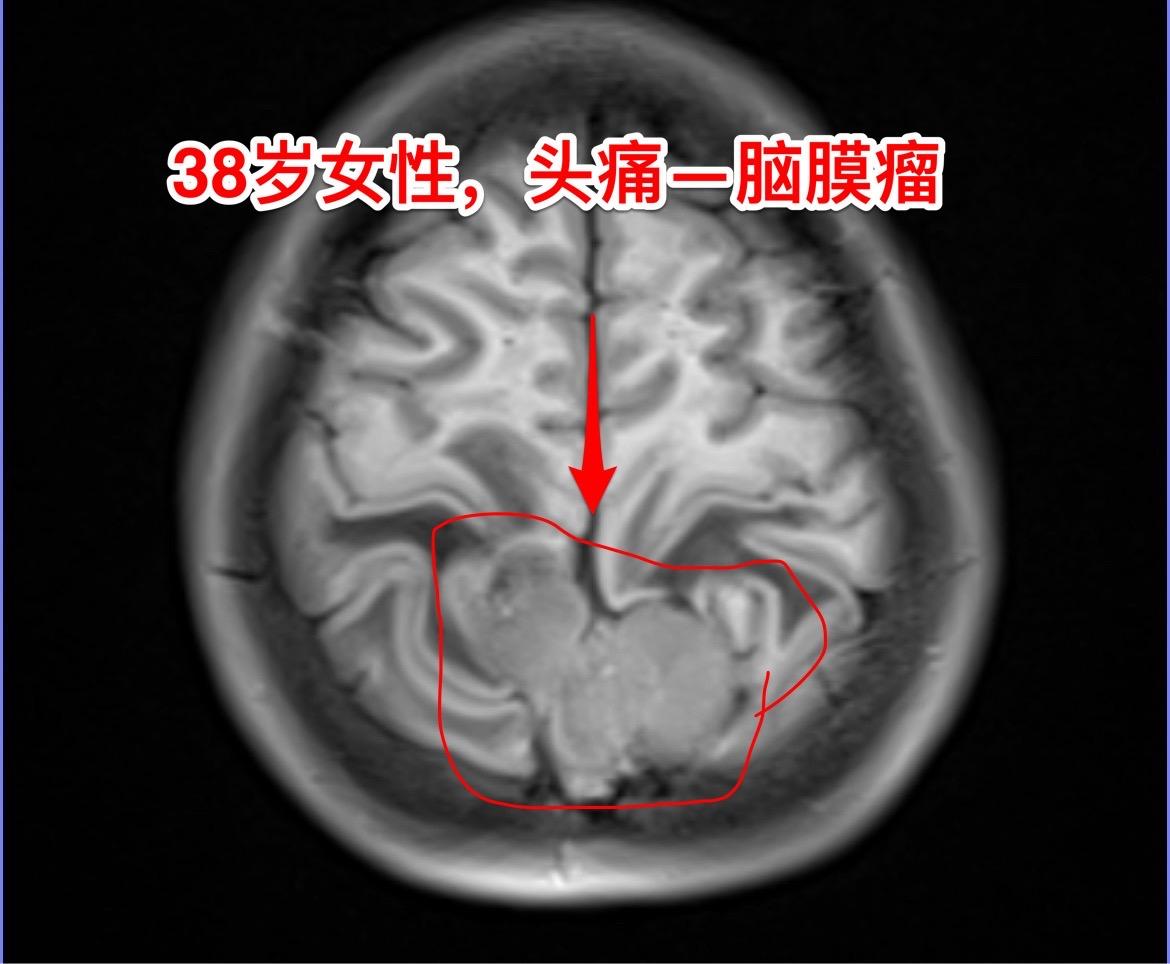

脑膜瘤的病理诊断—-需要格外关注。绝大多数的脑膜瘤都是良性肿瘤,小部分脑膜瘤是非典型的,也有一部分脑膜瘤呈恶性。 这个38岁湖北女性,因为头痛发现脑膜瘤。磁共振显示脑膜瘤周围有大范围的脑水肿,手术过程中发现肿瘤侵蚀了颅骨,将颅骨吃透了。直观的感受是:这个脑膜瘤是不是呈恶性趋势? 病理报告这个脑膜瘤是WHO1级,是良性肿瘤。只是Ki67指标稍高,以后需要定期复查。 这个病人手术后没有出现下肢活动无力症状,很快就能下地活动。这个位置的手术比颅咽管瘤手术要轻松许多,